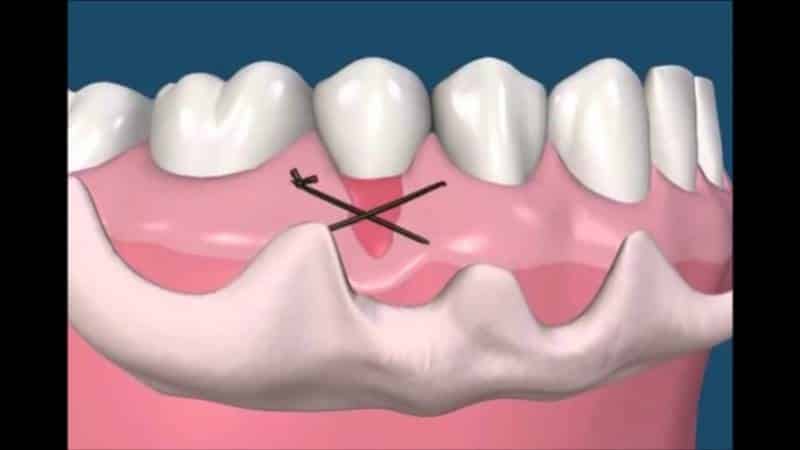

Метод лотерального лоскута. Этот подход применяется на ранних и средних стадиях заболевания, когда еще имеются участки здоровых тканей. Хирург-стоматолог накладывает лоскут на корни зубов, тем самым уменьшая рецессию на 1-2 мм. Преимущества: быстрая операция и короткий период восстановления. Недостаток: необходимость забирать лоскут-донор из здоровой области, что может вызывать дискомфорт у пациента. Кроме того, существует риск отторжения или неправильного приживления трансплантированной ткани, что может негативно сказаться на внешнем виде.

| Латерально смещенный лоскут | Перемещение десны с соседнего зуба на область рецессии. | Преимущества: Отсутствие донорской зоны, хороший эстетический результат. Недостатки: Ограниченное применение, может вызвать рецессию на донорском зубе. |